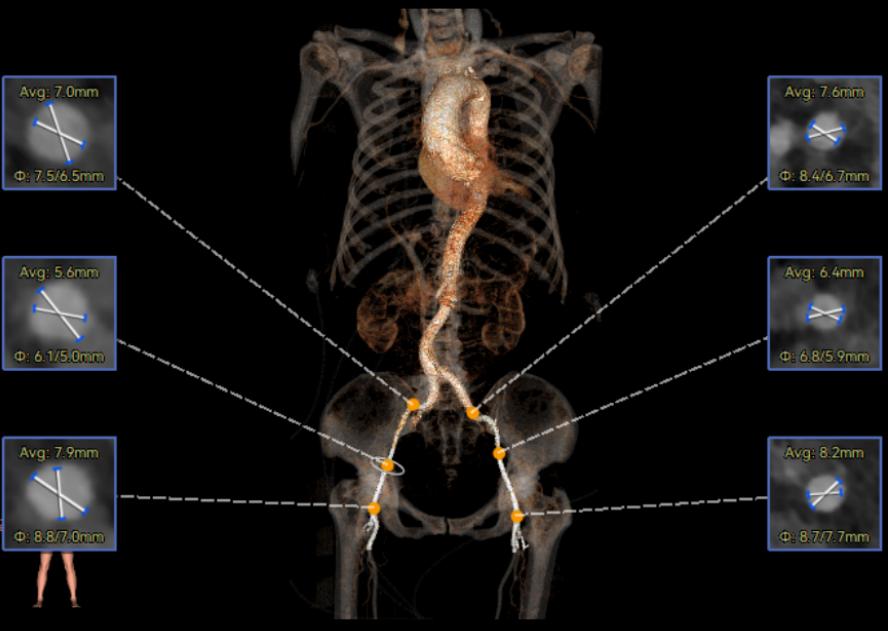

术前CT

Type1型二叶瓣,L-R融合,瓣叶轻度钙化,主要分布在无窦瓣叶边缘处,主动脉瓣环径23.6mm,LVOT20.6mm,呈收口型;双侧冠脉开口高度可,窦部空间大,VTC距离够,预估冠脉低风险,STJ、升主动脉内径增宽。右冠起源于左窦;主动脉水平夹角65.6°,横位心,主动脉弓角、弓距可。外周入路无明显迂曲,无明显钙化,双侧股动脉内径可,均能通过20F大鞘,右股低分叉。

推荐右侧股动脉为主入路,左侧股动脉为辅助入路,使用20F大鞘,推荐选择AV26瓣膜,备AV23瓣膜,18mm球囊预扩/不预扩,最终理想位置瓣下2mm。